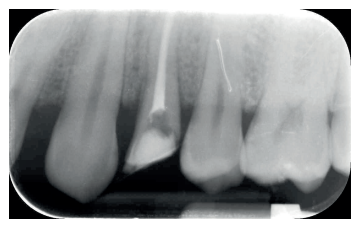

Se presenta en el Máster en Cirugía Oral, Implantología y Periodoncia de la Universidad Alfonso X El Sabio (Madrid, España) un paciente de 24 años derivado para exodoncia del primer premolar superior izquierdo y colocación inmediata de implante debido a una fractura corono-radicular como consecuencia de caries asintomática, con margen distal 2 mm subgingival y limitada estructura remanente (Figuras 1 y 2). Después de un estudio completo del caso, en colaboración con el Máster en Endodoncia de la misma facultad, se planificó la realización de la extrusión quirúrgica, endodoncia y posterior rehabilitación del diente. Dentro de este estudio resultaron de vital importancia las pruebas radiológicas, compuestas por radiografías periapicales y CBCT, que confirmaron la compatibilidad de la anatomía radicular con la realización de una extrusión mínimamente traumática.

con fractura corono-radicular.

fractura corono-radicular.